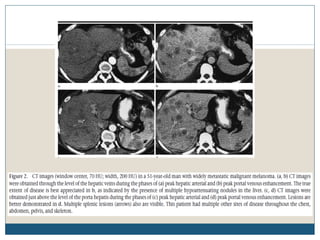

Fígado

 O fígado é um local comum de doença metastática, com séries de autópsia

sugerindo a presença de envolvimento hepático em até 58% dos pacientes

com melanoma metastático.

 Metástases hepáticas podem aparecer parcialmente calcificadas ou

hemorrágicas, e se for grande, pode conter áreas de necrose. O padrão de

reforço após a injecção de contraste pode ser uniforme, heterogêneo, ou em

forma de anel.

 Enquanto TC é o procedimento inicial de escolha para a imagiologia

anatómica do fígado, a ressonância magnética pode ser útil na identificação

de lesões solitárias tais como hemangiomas ou outras entidades benignas.

 Em imagens de RM, lesões metastáticas aparecem como áreas de hipossinal

em T1 e sinal moderadamente elevado em T2, enquanto hemangiomas são

caracteristicamente bem circunscritos.

 No ultra-som, metástases de melanoma são tipicamente hipoecóicas, e

hemorragia deve ser suspeitada se as lesões aparecerem heterogêneas.

 A metástase hepática subcapsular de melanoma pode ser uma causa rara

de um hematoma subcapsular ou hemorragia peritoneal.

Fígado  O fígadoé um local comum de doença metastática, com séries de autópsia sugerindo a presença de envolvimento hepático em até 58% dos pacientes com melanoma metastático.  Metástases hepáticas podem aparecer parcialmente calcificadas ou hemorrágicas, e se for grande, pode conter áreas de necrose. O padrão de reforço após a injecção de contraste pode ser uniforme, heterogêneo, ou em forma de anel.  Enquanto TC é o procedimento inicial de escolha para a imagiologia anatómica do fígado, a ressonância magnética pode ser útil na identificação de lesões solitárias tais como hemangiomas ou outras entidades benignas.  Em imagens de RM, lesões metastáticas aparecem como áreas de hipossinal em T1 e sinal moderadamente elevado em T2, enquanto hemangiomas são caracteristicamente bem circunscritos.  No ultra-som, metástases de melanoma são tipicamente hipoecóicas, e hemorragia deve ser suspeitada se as lesões aparecerem heterogêneas.  A metástase hepática subcapsular de melanoma pode ser uma causa rara de um hematoma subcapsular ou hemorragia peritoneal.